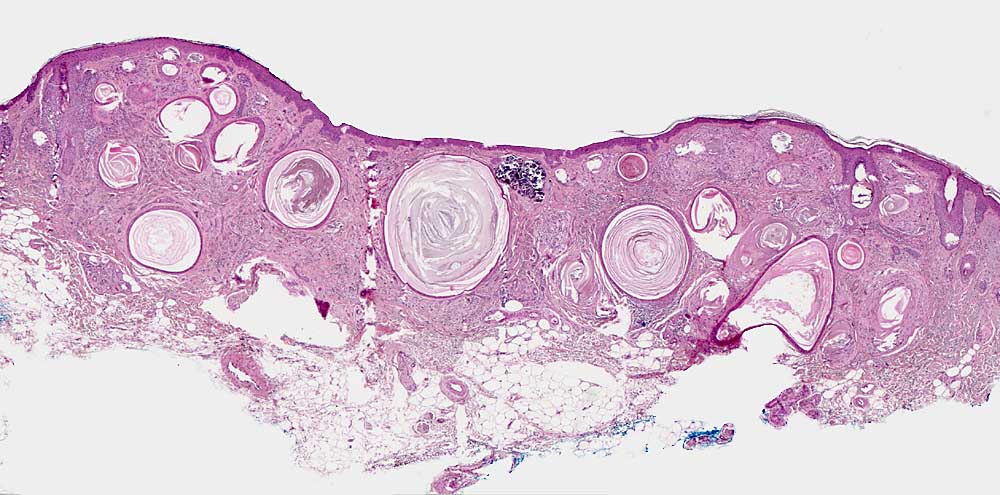

PathoPic – image database / PathoPic ID 6876 - Desmoplastisches Trichoepitheliom

Desmoplastisches Trichoepitheliom

benigner Tumor

Haut, Kopf

Haut

Teils rupturierte milienartige Epidermiszysten. Stränge und kleine Nester basaloider Zellen in der oberen retikulären Dermis. Zellarmes desmoplastisches Stroma. Fokale Verkalkungen (Schnittartefakte aufgrund der Verkalkungen). Die Subkutis ist ausgespart. Keine Entzündung.

4mm grosse derbe Papel mit erhabenem Rand und eingesenktem Zentrum im Gesicht

Histologie

25